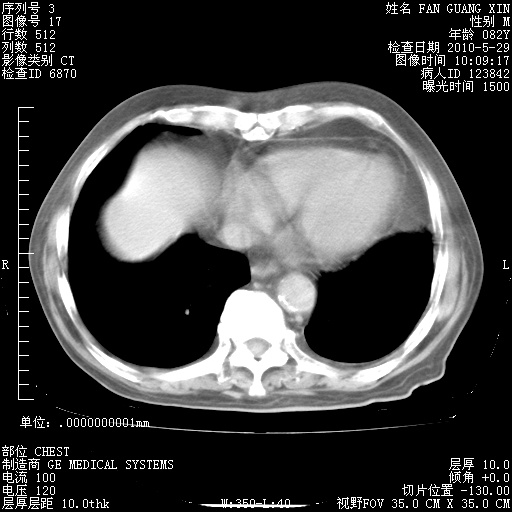

再治疗10天后的肺部CT 纵膈窗